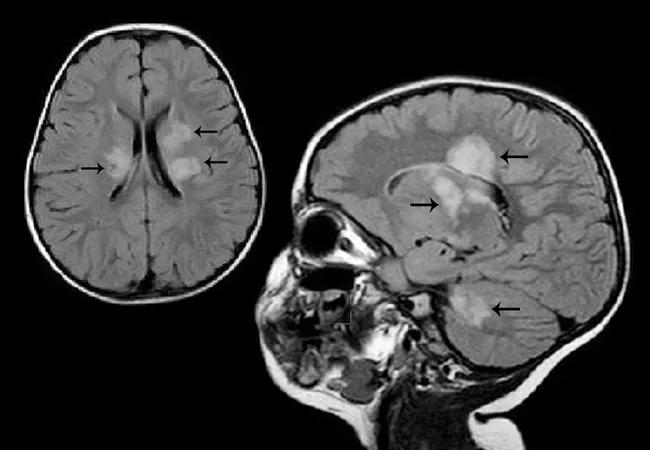

Despite the growing number of disease-modifying therapies (DMTs) for multiple sclerosis (MS), only one is approved for use in children. This is a challenge for physicians like Aaron Abrams, MD, and Mary Rensel, MD, who see increasing evidence that early, targeted treatment of pediatric-onset MS (POMS) can help offset long-term disability. Dr. Abrams is a pediatric MS and neuroimmunology specialist in the Center for Pediatric Neurosciences and Dr. Rensel is an MS expert in the Mellen Center for Multiple Sclerosis, both within Cleveland Clinic’s Neurological Institute.